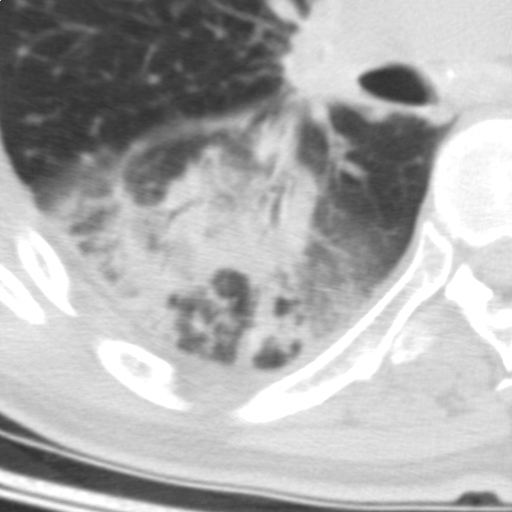

以下是引用随光逐影在2009-5-1 13:53:00的发言:[br]考虑为:1)两肺血行播散型肺结核;2)右肺下叶炎症感染。3)右侧胸膜增厚。